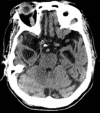

Neurodegenerative diseases are a devastating group of disorders that can be difficult to accurately diagnose. Although these disorders are difficult to manage owing to relatively limited treatment options, an early and correct diagnosis can help with managing symptoms and coping with the later stages of these disease processes. Both anatomic structural imaging and physiologic molecular imaging have evolved to a state in which these neurodegenerative processes can be identified relatively early with high accuracy. To determine the underlying disease, the radiologist should understand the different distributions and pathophysiologic processes involved. High-spatial-resolution MRI allows detection of subtle morphologic changes, as well as potential complications and alternate diagnoses, while molecular imaging allows visualization of altered function or abnormal increased or decreased concentration of disease-specific markers. These methodologies are complementary. Appropriate workup and interpretation of diagnostic studies require an integrated, multimodality, multidisciplinary approach. This article reviews the protocols and findings at MRI and nuclear medicine imaging, including with the use of flurodeoxyglucose, amyloid tracers, and dopaminergic transporter imaging (ioflupane). The pathophysiology of some of the major neurodegenerative processes and their clinical presentations are also reviewed; this information is critical to understand how these imaging modalities work, and it aids in the integration of clinical data to help synthesize a final diagnosis. Radiologists and nuclear medicine physicians aiming to include the evaluation of neurodegenerative diseases in their practice should be aware of and familiar with the multiple imaging modalities available and how using these modalities is essential in the multidisciplinary management of patients with neurodegenerative diseases.©RSNA, 2020.